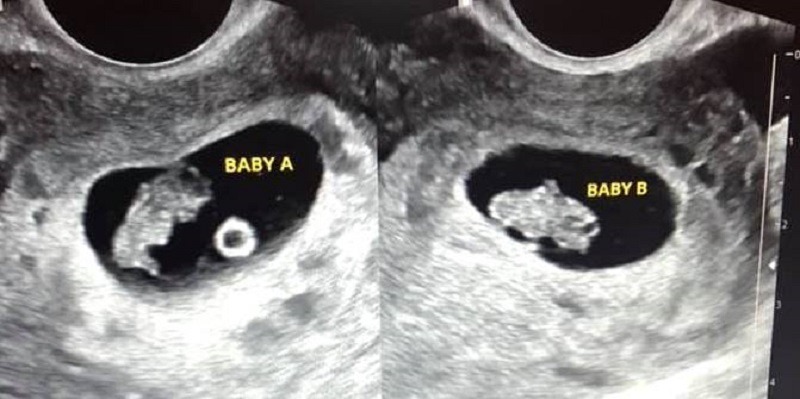

Siêu âm hoàn toàn có thể phát hiện thai đôi và là phương pháp chẩn đoán chính xác nhất hiện nay. Từ tuần thai thứ 6–8, siêu âm đầu dò âm đạo hoặc siêu âm bụng có thể thấy rõ hai túi thai hoặc hai phôi thai trong tử cung. Bác sĩ cũng có thể xác định thai đôi cùng trứng (chung nhau thai) hay khác trứng (hai nhau thai riêng biệt), điều này rất quan trọng để theo dõi các nguy cơ trong thai kỳ. Ngoài việc đếm số thai, siêu âm còn giúp kiểm tra sự phát triển của từng thai, tình trạng nhau thai và lượng nước ối. Nhờ vậy, thai phụ mang song thai được chăm sóc và theo dõi sát sao hơn để phòng ngừa biến chứng.

Siêu âm có thể phát hiện thai đôi khá sớm, thường từ tuần thứ 6–8 của thai kỳ. Ở giai đoạn này, siêu âm đầu dò âm đạo giúp nhìn thấy rõ hai túi thai hoặc hai phôi thai trong tử cung. Với siêu âm bụng, thai đôi có thể được phát hiện muộn hơn một chút, khoảng tuần thứ 8–10 khi hai túi thai đã phát triển rõ ràng. Ngoài ra, siêu âm trong 3 tháng đầu cũng giúp xác định thai đôi cùng trứng hay khác trứng. Nếu siêu âm quá sớm (trước tuần 5), hình ảnh thai đôi có thể chưa rõ ràng nên cần theo dõi thêm.

- Tuần 6–8: Siêu âm đầu dò hoặc siêu âm bụng để xác định số túi thai, số phôi và tim thai.